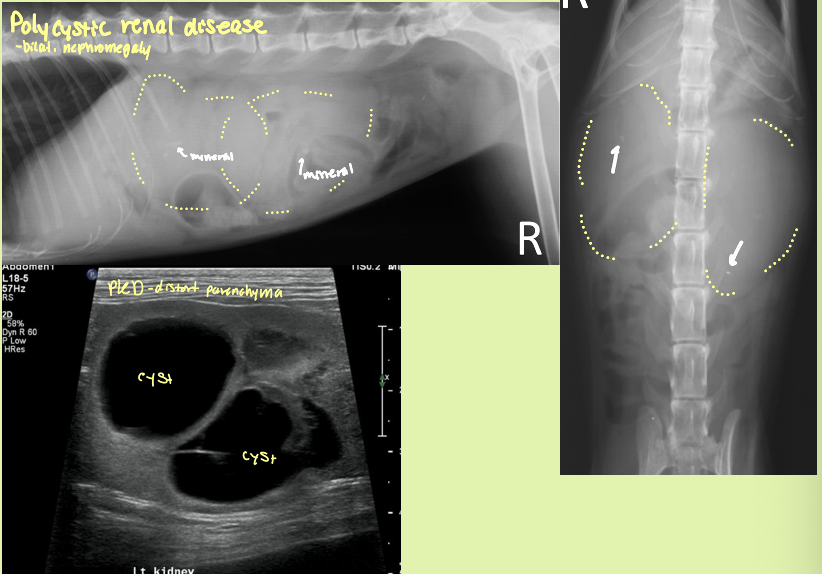

polycystic renal disease (PCRD) is heritable in what species and breed

persian cats - autosomal dominant

what organ likes to accumulate cysts with PCRD

kidneys and liver

what is the sequela of severe PCRD

chronic renal failure - parenchyma distorted and non-fxn

bilateral renomegaly with irregular margins with many cysts in the cortex that are anechoic with distal acoustic enhancement

PCRD